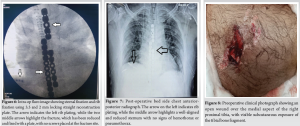

The patient was scheduled for open reduction and internal fixation using standard plating. The patient was taken to the operating theater after obtaining informed high-risk consent. General anesthesia was administered with endotracheal intubation, and broad-spectrum intravenous antibiotics were given preoperatively. The patient was positioned supine with a small bolster placed between the scapulae to mildly extend the thoracic spine and expose the anterior chest wall. A midline longitudinal incision was made to open the chest wall, allowing visualization of the fracture and examination of the underlying heart and lung tissue (Fig. 4). The sternal edges were realigned and approximated, any interposed soft tissue was removed, and a 3.5 mm straight locking reconstruction plate was applied for fixation (Fig. 5). Locked screws were placed in the proximal fragment, and standard screws were replaced with locked screws to ensure secure plate-screw fixation. Four locking screws were used on the distal-inferior side, and three locking screws on the proximal-superior side, all achieving a stable fixation (Fig. 6).

On the right side, the fractured 8th rib was reduced and stabilized with a 2 mm reconstruction plate. The wound was closed with a negative-pressure drain to prevent hematoma formation, which was removed after 48 h.Post-op X-ray (Fig. 7) shows well-aligned and reduced sternum with no evidence of pneumothorax or hemothorax.The open wound on the medial aspect of the proximal tibia (Fig. 8) was initially managed with urgent debridement, for the proximal tibia 1/3rd shaft fracture (Fig.-9) application of an external fixator (Fig. 10), and initiation of negative pressure wound therapy. After ensuring the wound was healthy, a flap coverage procedure was done by the plastic surgery team. Following flap maturation, the external fixator was removed, and the patient underwent closed reduction and internal fixation using tibial interlocking (intramedullary interlocking) nailing (Fig. 11).